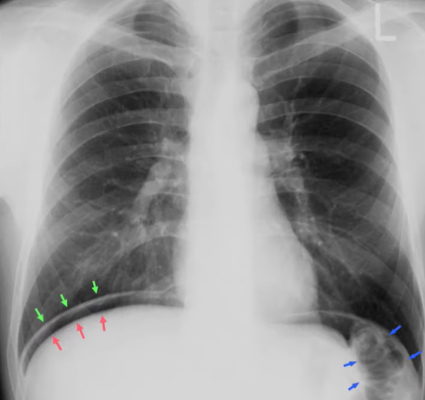

The red arrows indicate the upper border of the (BLANK).

A) Stomach

B) Liver

C) Heart

D) Kidney

Correct Answer:

To what structure are the arrows pointing?

A) Intestinal walls

B) Stomach

C) Kidney

D) Liver